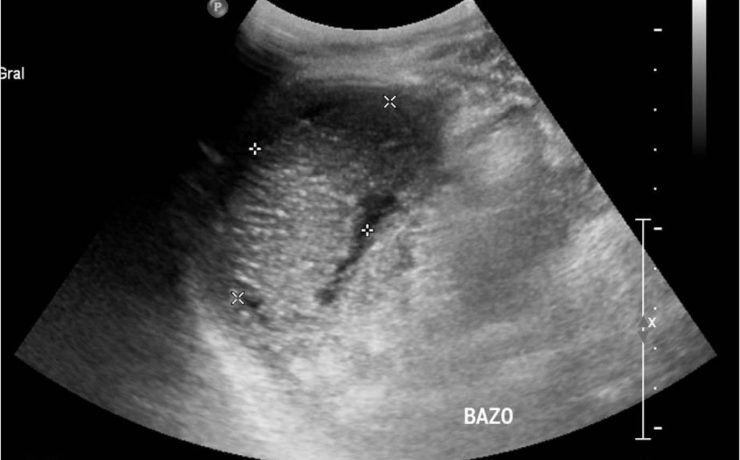

La vesícula biliar se divide en fundus, cuerpo y cuello, en el cuello puede haber un infundíbulo o “Bolsa de Hartmann” Puede haber falta de visualización por: Colecistectomía previa Contracción fisiológica Conducto de vesícula biliar fibrosado: colecistitis crónica Vesícula biliar llena de aire o colecistitis enfisematosa Agenesia Localización ectópica PATOLOGIA